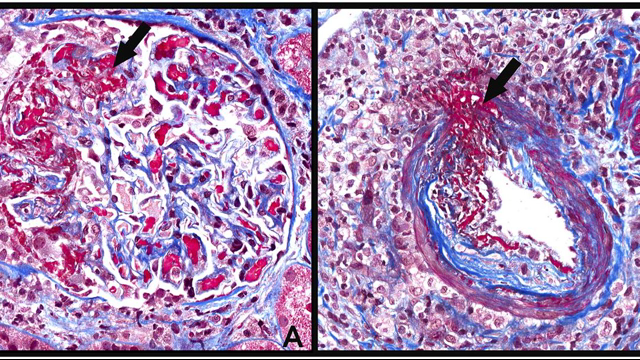

77-year-old man with a type 2 DM presents with worsening renal function and proteinuria